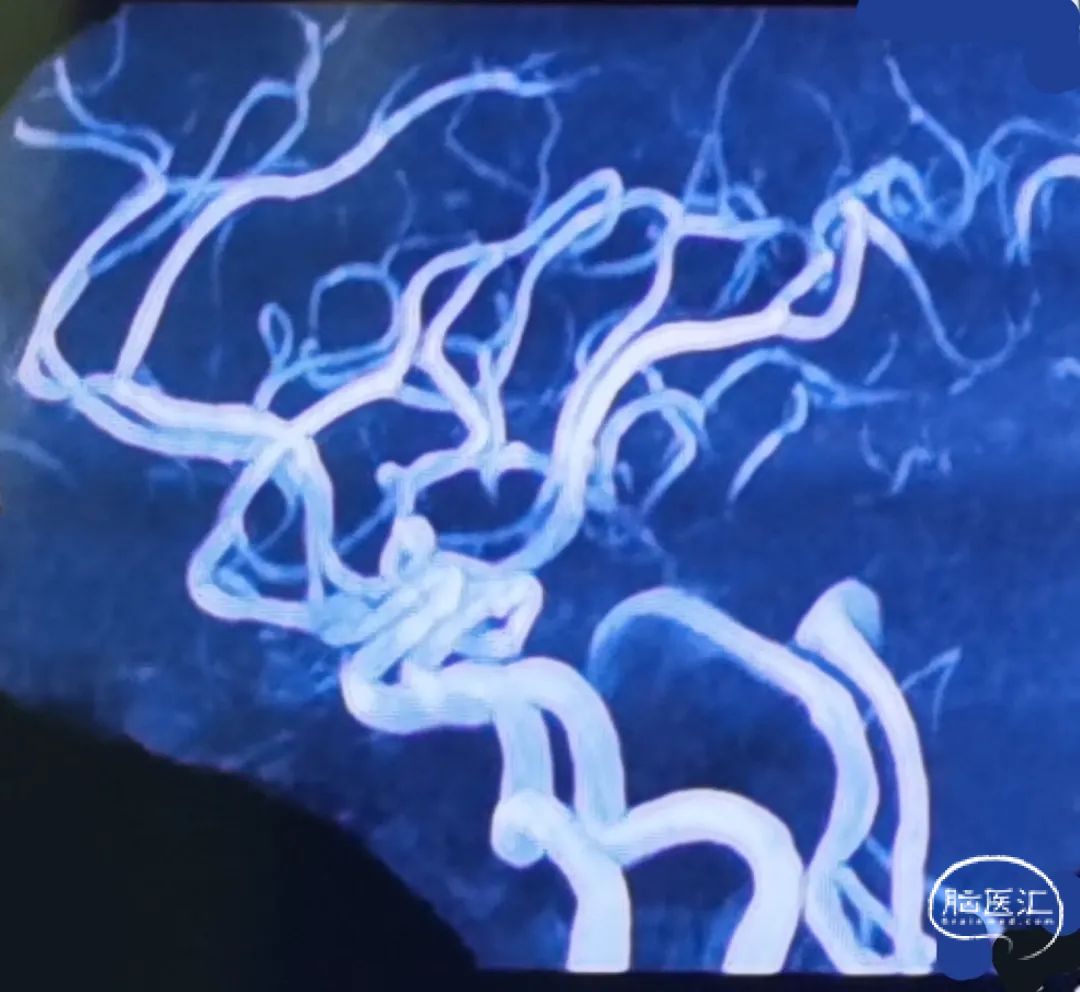

入院时头颅MRA

术后3个月MRA

术后3个月MRA复查提示:支架内血流通畅,动脉瘤体积进一步缩小。准备6-12月期间复查脑血管造影